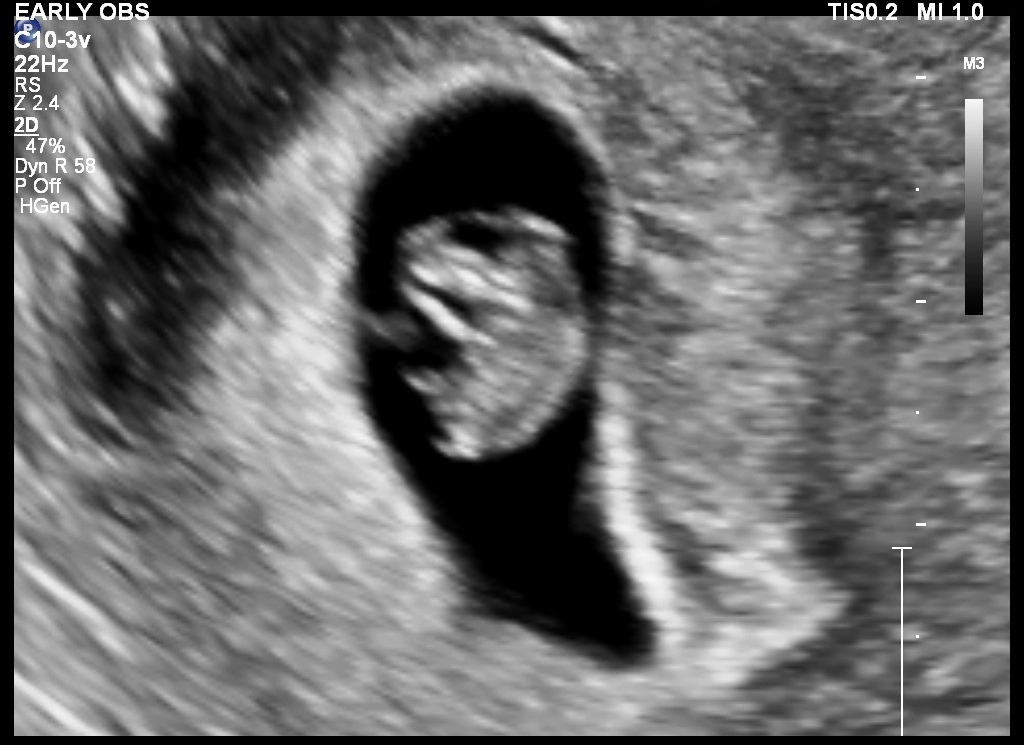

Early Pregnancy Sonography

Sonography is often asked for by the obstetrician to estimate the duration of pregnancy and to confirm viability of the pregnancy. Further sonographies can be scheduled based on the estimated gestational age.